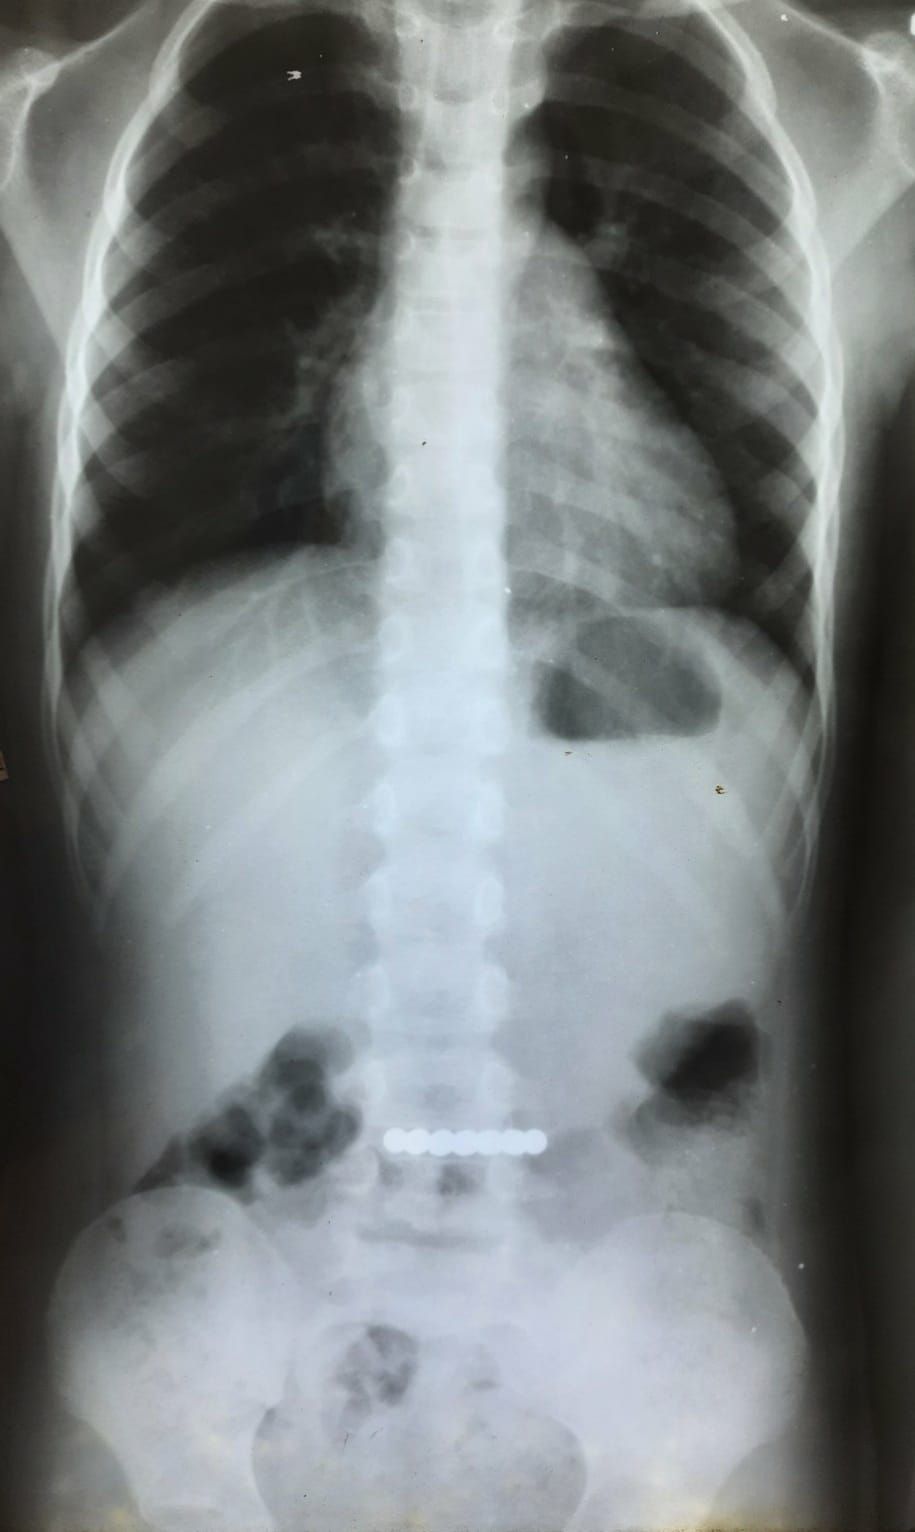

Как рассказала Наталья Щудро, ребенок проглотил 12 магнитных шариков. Игрушка застряла у маленького пациента в желудке. К счастью, врачи своевременно провели диагностику и обнаружили проблему.

С помощью эндоскопического вмешательства шарики вытащили из желудка, и жизни маленького пациента больше ничего не угрожает. Отметим, что дети часто проглатывают такие игрушки и попадают в больницу.

И снова магнитные шарики. Хорошо, когда все хорошо кончилось! Благодаря своевременному реагированию хирургической службы проведено эндоскопическое вмешательство и удалено постороннее тело из желудка, - отметила Наталья.